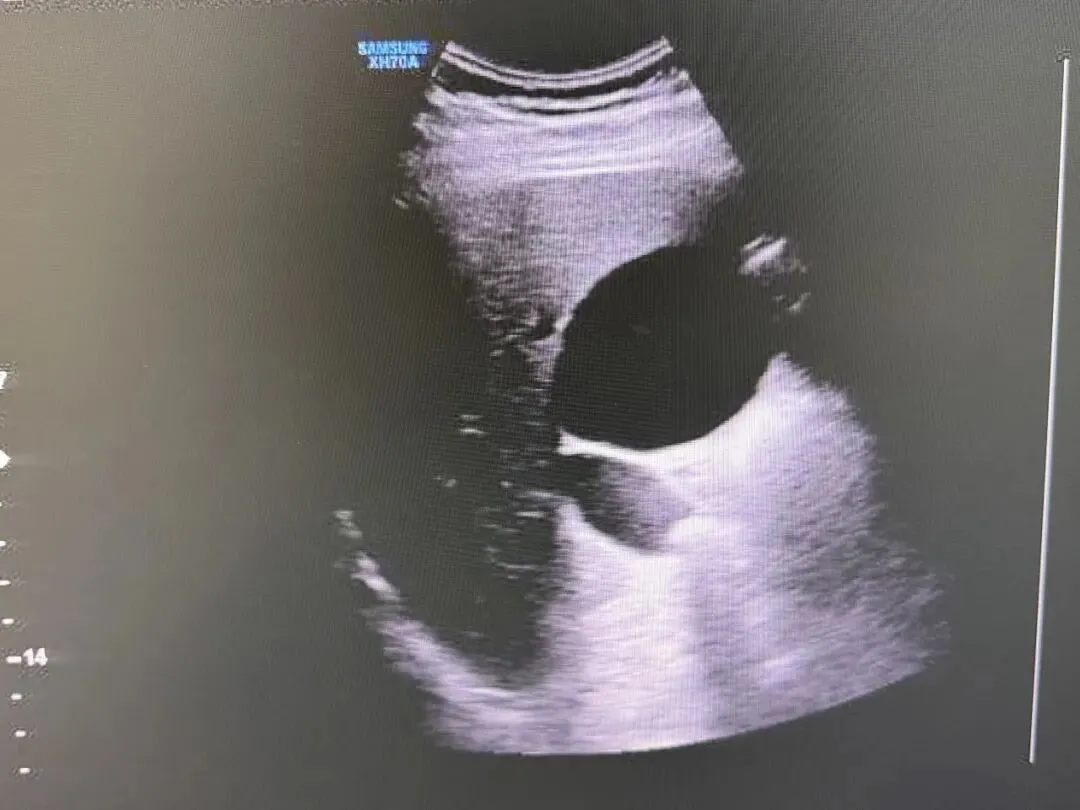

胆囊壁增厚,胆囊内透声差,其内稀疏或密集的细小或粗大光点

胆囊肿大,胆囊壁增厚,胆囊内透声差,充满稀疏或密集的细小或粗大光点

囊壁增厚,呈“双边影”